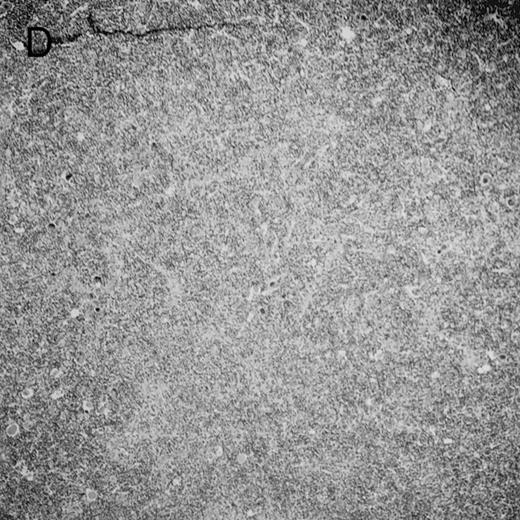

Histologic findings. Organs were collected at different times after BMT and tissue sections were stained with hematoxylin and eosin. Original magnifications for spleen (left) and liver (right) are ×40 and ×100, respectively. (A) B6 mice receiving FVB BM plus EpTK T cells. (B) Control group receiving BM only.

(C) B6 mice receiving FVB BM plus EpΔTK T cells and treated with GCV. (D) B6 mice receiving FVB BM plus EpΔTK T cells, treated with GCV, and developing a late onset GVHD (day 54).

FVB BM-grafted B6 mice: a model of lethal GVHD.We developed a model of GVHD resulting in 100% mortality soon after BMT using FVB mice, a strain not previously used as BM donors in experimental allogeneic BMT. We tested different combinations of recipient irradiation doses, as well as injected BM cell and CD3+ peripheral T-cell numbers. When 10-Gy–irradiated B6 mice were reconstituted with 107 FVB BM cells, we observed prolonged survival, whereas all ungrafted animals died before day 16 (Fig 2). In these conditions, more than 98% of splenocytes were of donor origin (Fig 3A). When 107 CD3+ peripheral T cells from mice of FVB genetic background were added to the FVB BMT, all animals died of GVHD between days 7 and 34 (Fig 2). Similar results were obtained using either PBS-treated mice receiving EpTK or EpΔTK peripheral T cells or GCV-treated mice receiving FVB nontransgenic peripheral T cells. Notably, this observation also indicates that both TK- and ΔTK-expressing T cells in the absence of GCV are fully competent to induce a lethal GVHD. Histopathologic examination of spleen and liver of these animals showed characteristic GVHD lesions such as (1) architecture disruption, necrosis, and congestion in the spleen; (2) hepatic periportal necrosis; (3) mononuclear portal infiltrates; and (4) endothelialitis of portal or centrolobular veinules (Fig 4A). By comparison, B6 mice receiving only FVB BM had a normal histology (Fig 4B).

On the other hand, 5 of 19 mice exhibited signs suggesting the occurrence of a delayed GVHD (Table 1). Clinically, these animals presented weight loss and/or skin lesions on ears, neck, limbs, or abdomen, but only after day 40. In the absence of any further GCV treatment, 2 mice died 14 and 29 days after the occurrence of these signs (Table 1A) with histological signs of severe GVHD (Fig 4D). These results suggest that, in these mice, the 7-day GCV treatment was sufficient to prevent early, but not delayed GVHD.